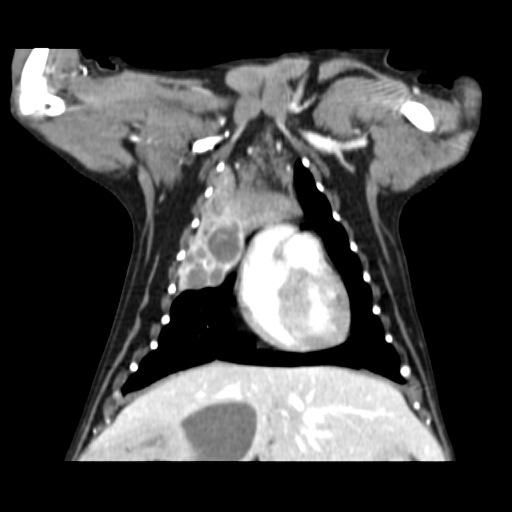

엑스레이 사진과 CT 사진(흉부 앞, 우측 옆)은 첨부하였습니다.

폐 우측 위쪽에 원발성 암이 발생한 것으로 보였습니다.

식도와 심장을 눌러서 기침을 발생시켰습니다.

나쁜 소식은 심장과 혈관이 위치한 안 좋은 부위에 암이 있다는 것이고,

좋은 소식은 심장과 혈관과 아직 붙지 않고 떨어져 있다는 것이었습니다.